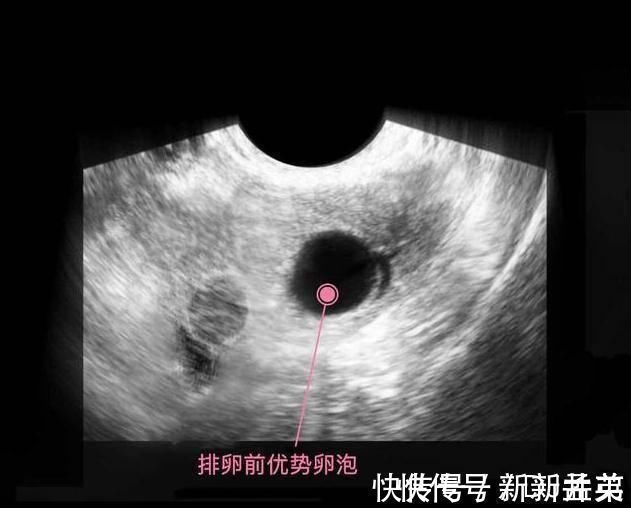

上图是第1周,卵子排出了优势卵泡,等待优质的精子冲破重重阻碍,卵子也不是一动不动,它从卵巢出来会用到输卵管里,在此等候精子先生12-24个小时,如果相遇,那么就结合成受精卵,受孕就成功了。